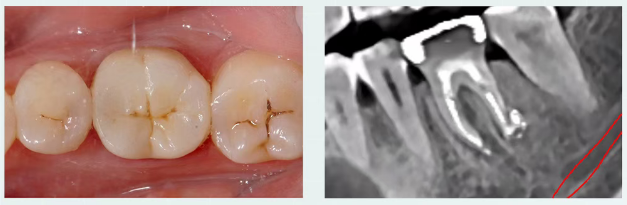

2个月复查

治疗后两月完成最终修复,临床检查无症状,行使功能良好;通过根尖片可见根尖低密度暗影有改善,根分叉处及牙周膜增宽影像呈现愈合趋势;

除了糊剂些许溢出外,一切良好,得益于nRootSP良好的性能。